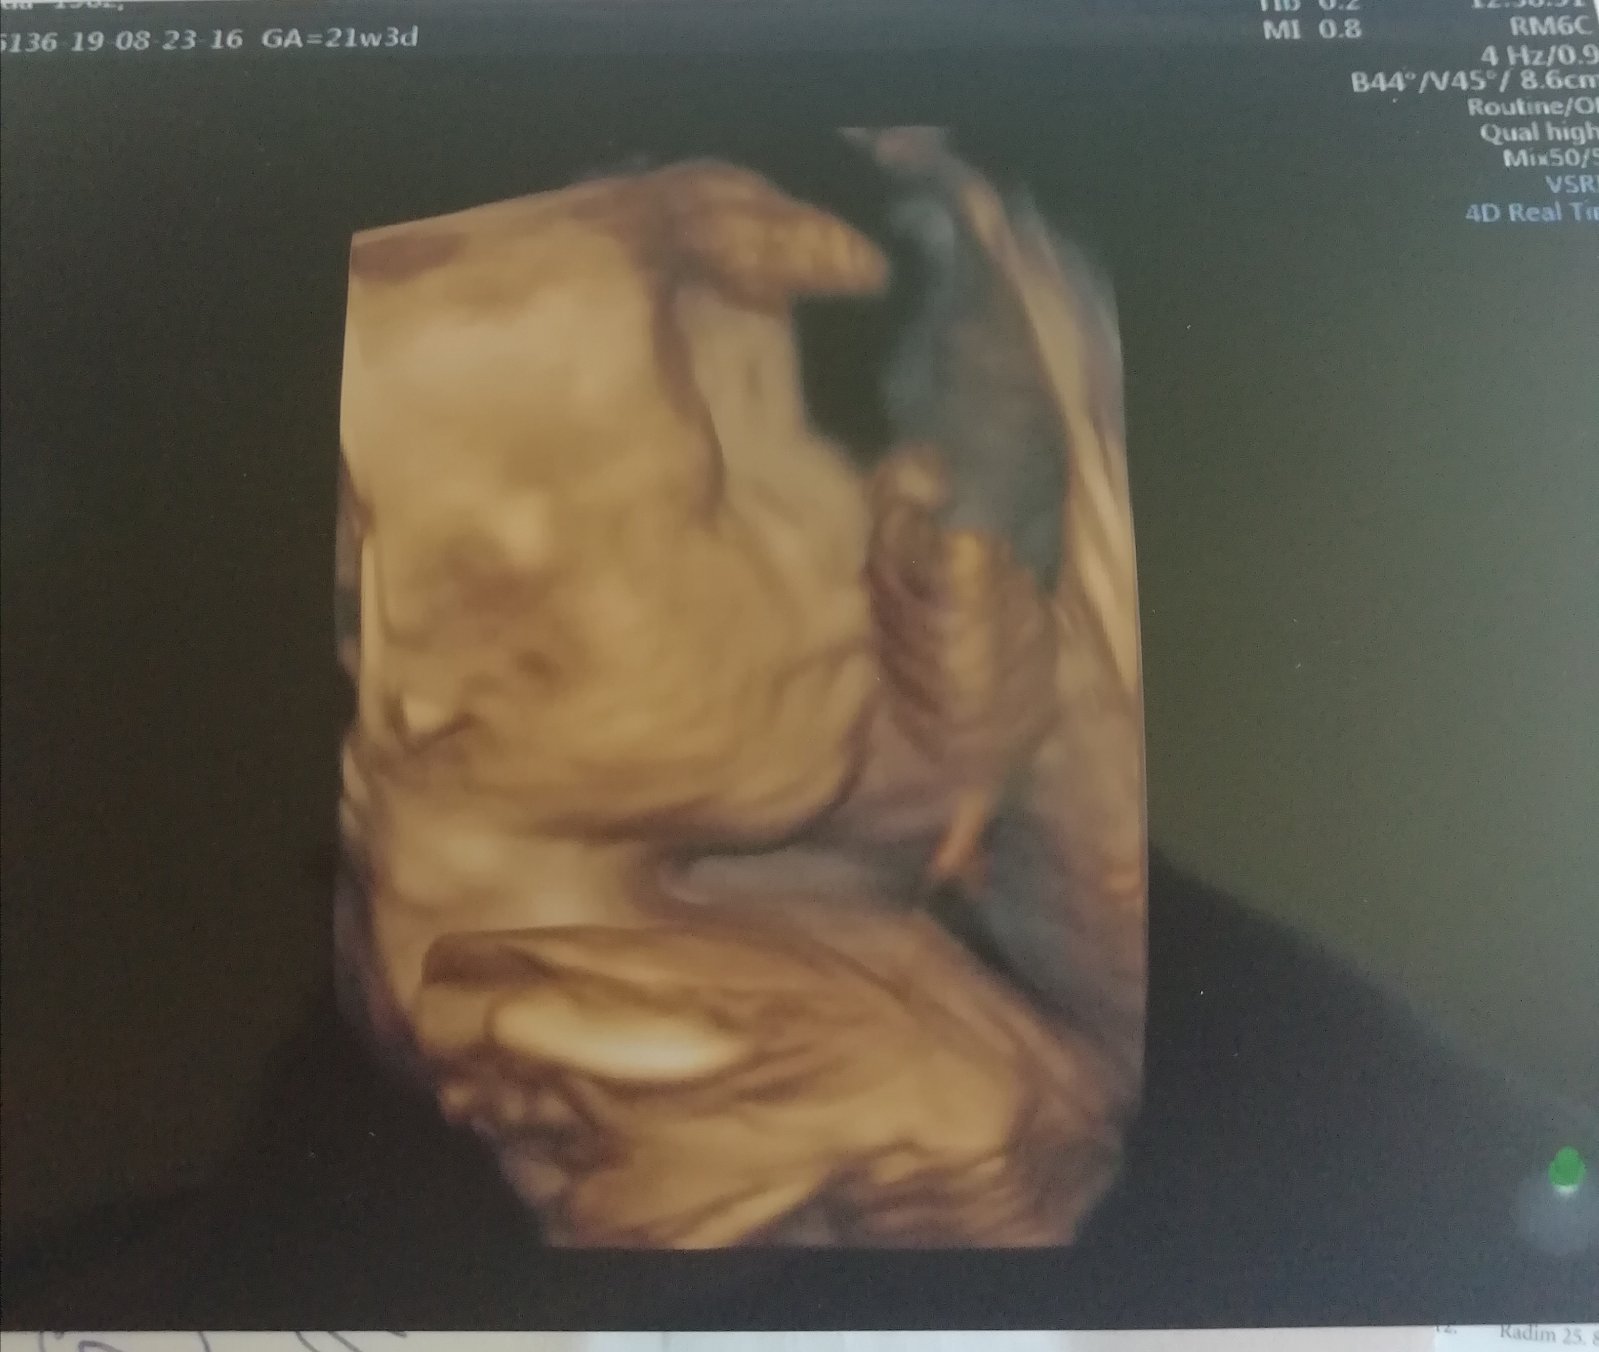

Ahoj holky, tak my máme 2. screening za sebou, byli jsme včera. Vše je v naprostém pořádku a na svém místě, vše funguje tak, jak má, opět potvrzena holčička a bylo super ji opět vidět 🙂 Pán doktor ultrazvuk přepnul na chvíli i na 3D a je to mazec vidět už ty rysy obličejíčku 🙂 Jinak my chodíme do Brna do Prenatalu, platili jsme 1200 Kč a dostali jsme 3D fotečku a nahrávku celého ultrazvuku na CD. Tak pak pisnite váš zážitek 😇

@jennas Tak pak šupní nějakou fotečku z toho 4D, pokud budeš mít, ju? 🙂 My se teda na ty další ultrazvuky (3D a 4D) už objednávat nebudeme. Teď už budeme jen chodit do poradny na gyndu...

Ahojky holky, tak u nás na druhem screeningu vsechno na jednicku🙂 Mame na 100% pindu pry🙂 tak uz tomu zacinam verit teda🙂 akorat byl celou dobu v poloze sklapovacka, nohy i ruce pred oblicejem, takze rysy smolik a jsme preobjednani na ten 25tt, tak doufam, ze to bude spolupracovat🙂 🙂

@laloogrey @jennas Ahoj holky, tak to oběma gratuluju k pozitivním zprávám, to je moc dobře! 😍 Jsem ráda, že se nám daří, ale zároveń to klepu!!🙂 Já byla v pondělí na kontrole a včera na 3D utz. Na kontrole ok, jsem ve 22+1 a nahoře mám cca 4,2 kg, tak snad je to ok. Nikdo k tormu nic neříkal A vyfasovala jsem žádanku na cukrovku, tak za 14 dní se mám objednat. Tobě @laloogrey držím palce, aby pro tebe ta zvýšená hodnota nic neznamenala a bylo všechno ok!! 😉Jinak já vám taky ukážu naši malou princeznu na fotečce, co jsme dostali🥰